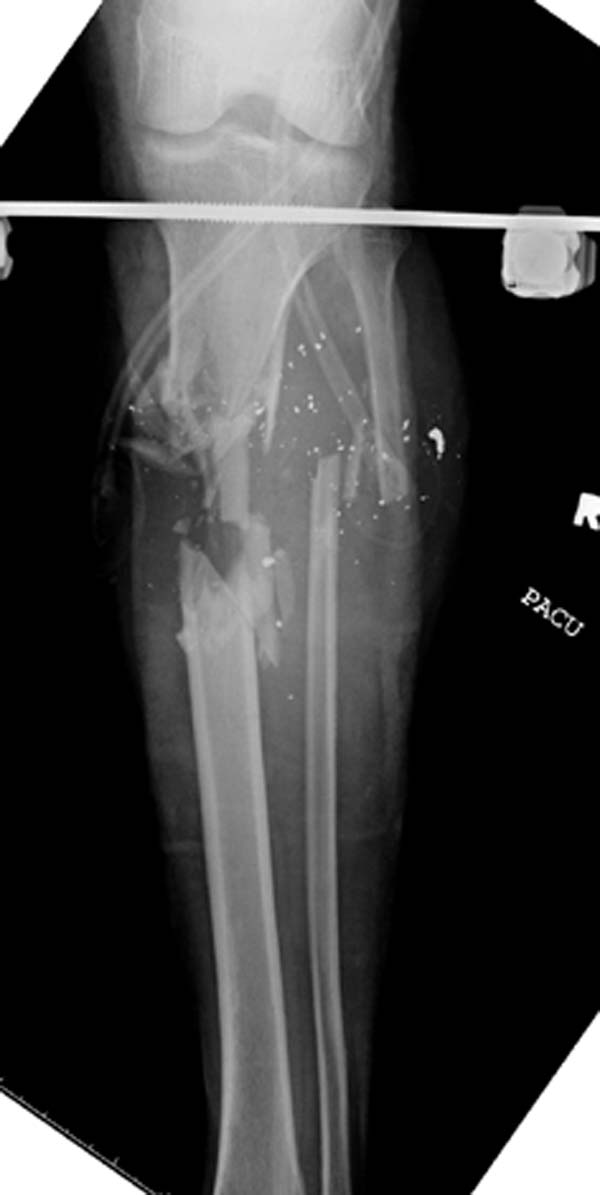

У моего б-го обширна ран по всей передней половине с/3 голени, в основном гранулирует, но область перелома по передне-медиалной поверхности открыта 2 на 2 см

Вид покачественне

Вопрос: у вас рубец в в/3 голени - это "случайно" не интармедуллярный гвоздь стоит?

Спасибо, Др.Дмитриев! Да у Вас просто орлиный глаз! :)) Действительно, там гвоздь без рассверливания, ведь перелом был закрытый. Я думаю, некроз пошел от удара бампером автомибиля

И в ране видна область перелома. Трепанации так близко к перелому не навредят? Кровушки вакуумом слишком не потеряем из костнмозгового? Как насчет гвоздя и вакуума?

Снимки от 23-го июня

23-е июня